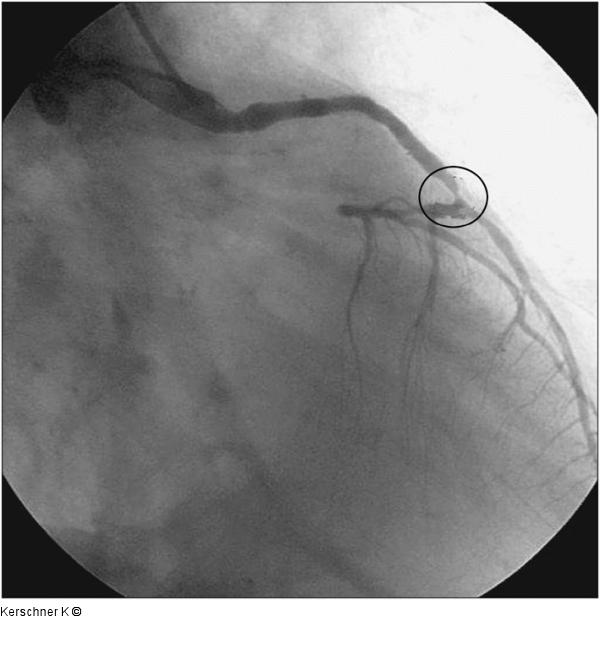

Abbildung 1: Aortokoronarer Venenbypass - RAO-Projektion Aortokoronarer Venenbypass zum LAD mit 90%iger Stenose an der distalen Anastomose. RAO-Projektion |

Aortokoronarer Venenbypass zum LAD mit 90%iger Stenose an der distalen Anastomose. RAO-Projektion |